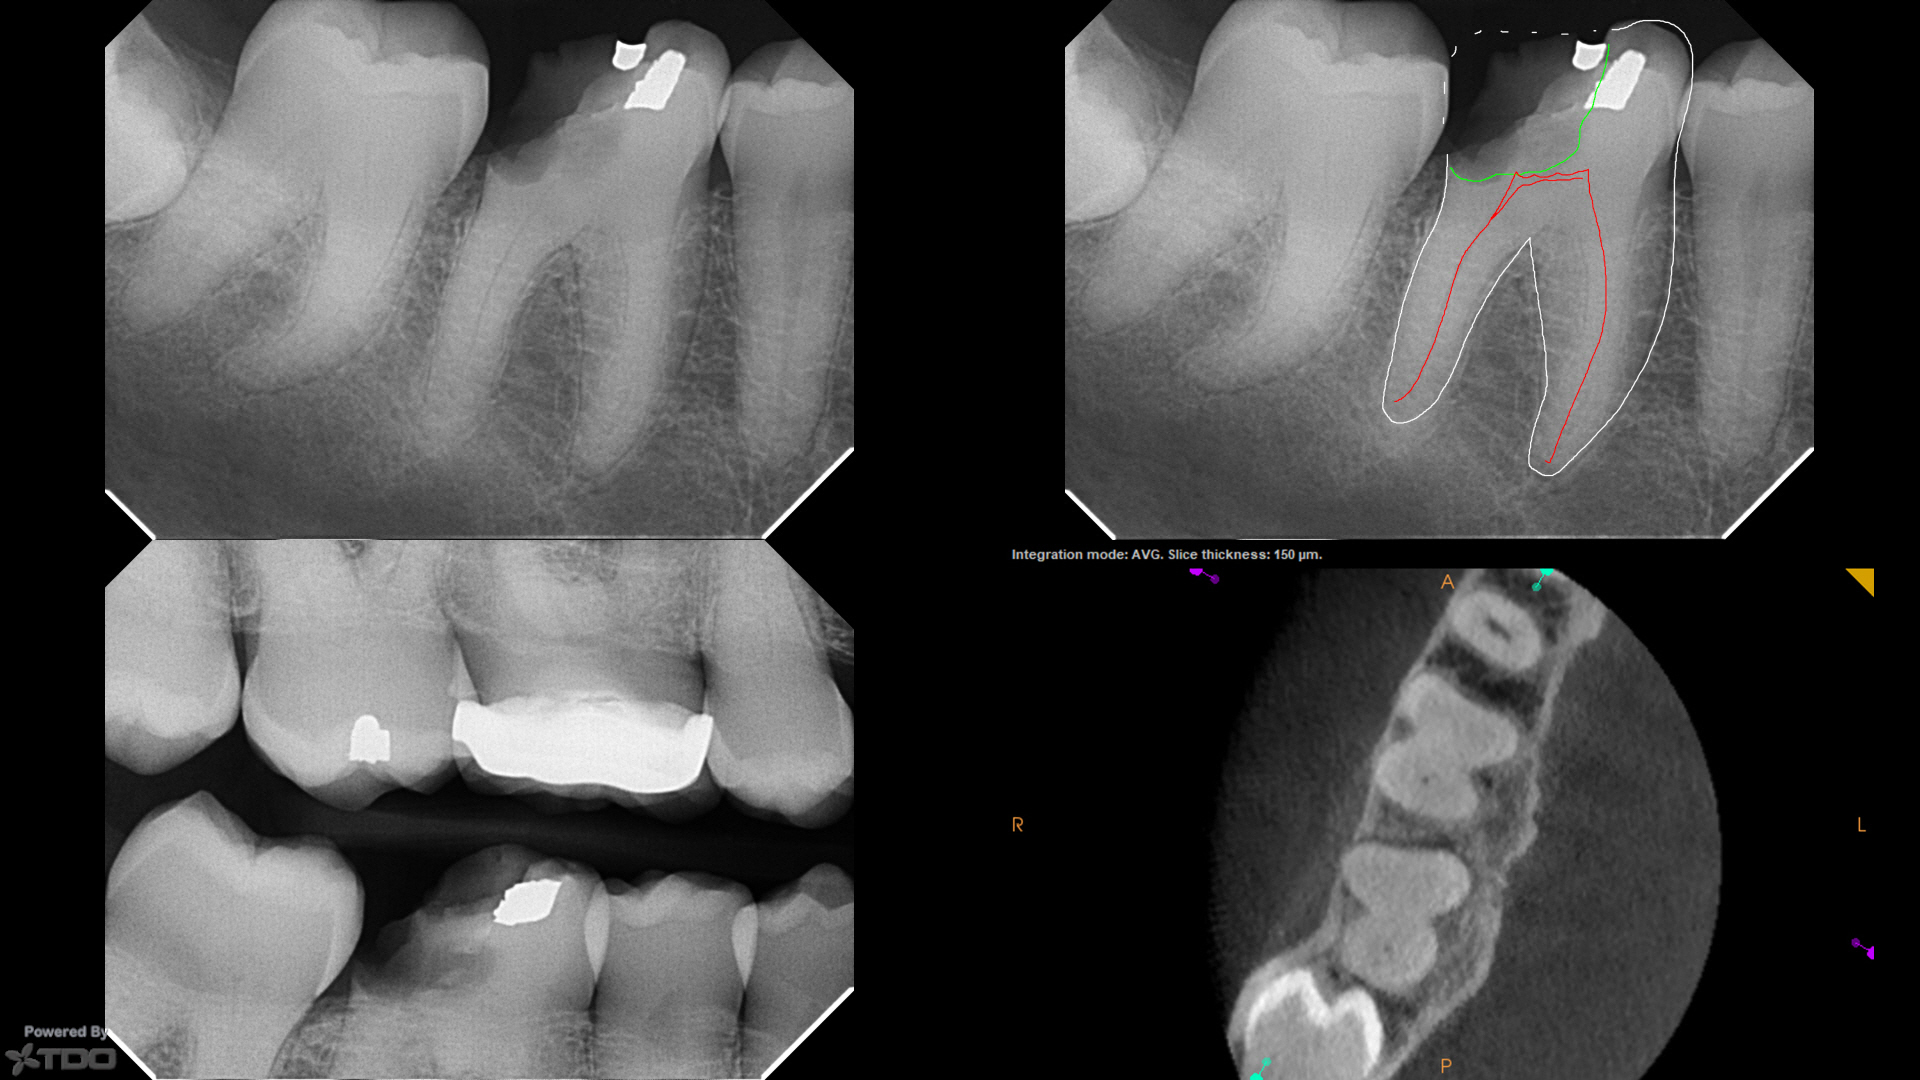

The very first step to mastering your dental health is conquering the mental game. The phrase "calcified root canal" sounds incredibly intimidating, but let's reframe it. If you are wondering how can calcified roots affect your root canal procedure, it simply means your tooth has built up extra layers of protection on the inside over the years. Because the space is narrower, your dental specialist just needs to use a microscope and a bit more time to clean it thoroughly. That is it! It is a precise, delicate process, not a painful one.